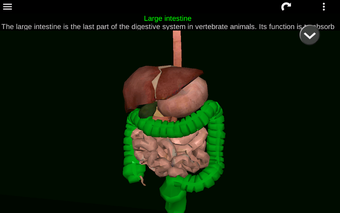

此应用程序显示人体器官的三维模型和所有器官的描述。

您可以触摸每个器官,如心脏、大脑、肺、生殖系统、肝脏、肠道、卵巢、睾丸、胃、肾脏等。

它对所有人都有用,甚至对学生也有用,因为每个解剖器官都以不同的颜色显示。